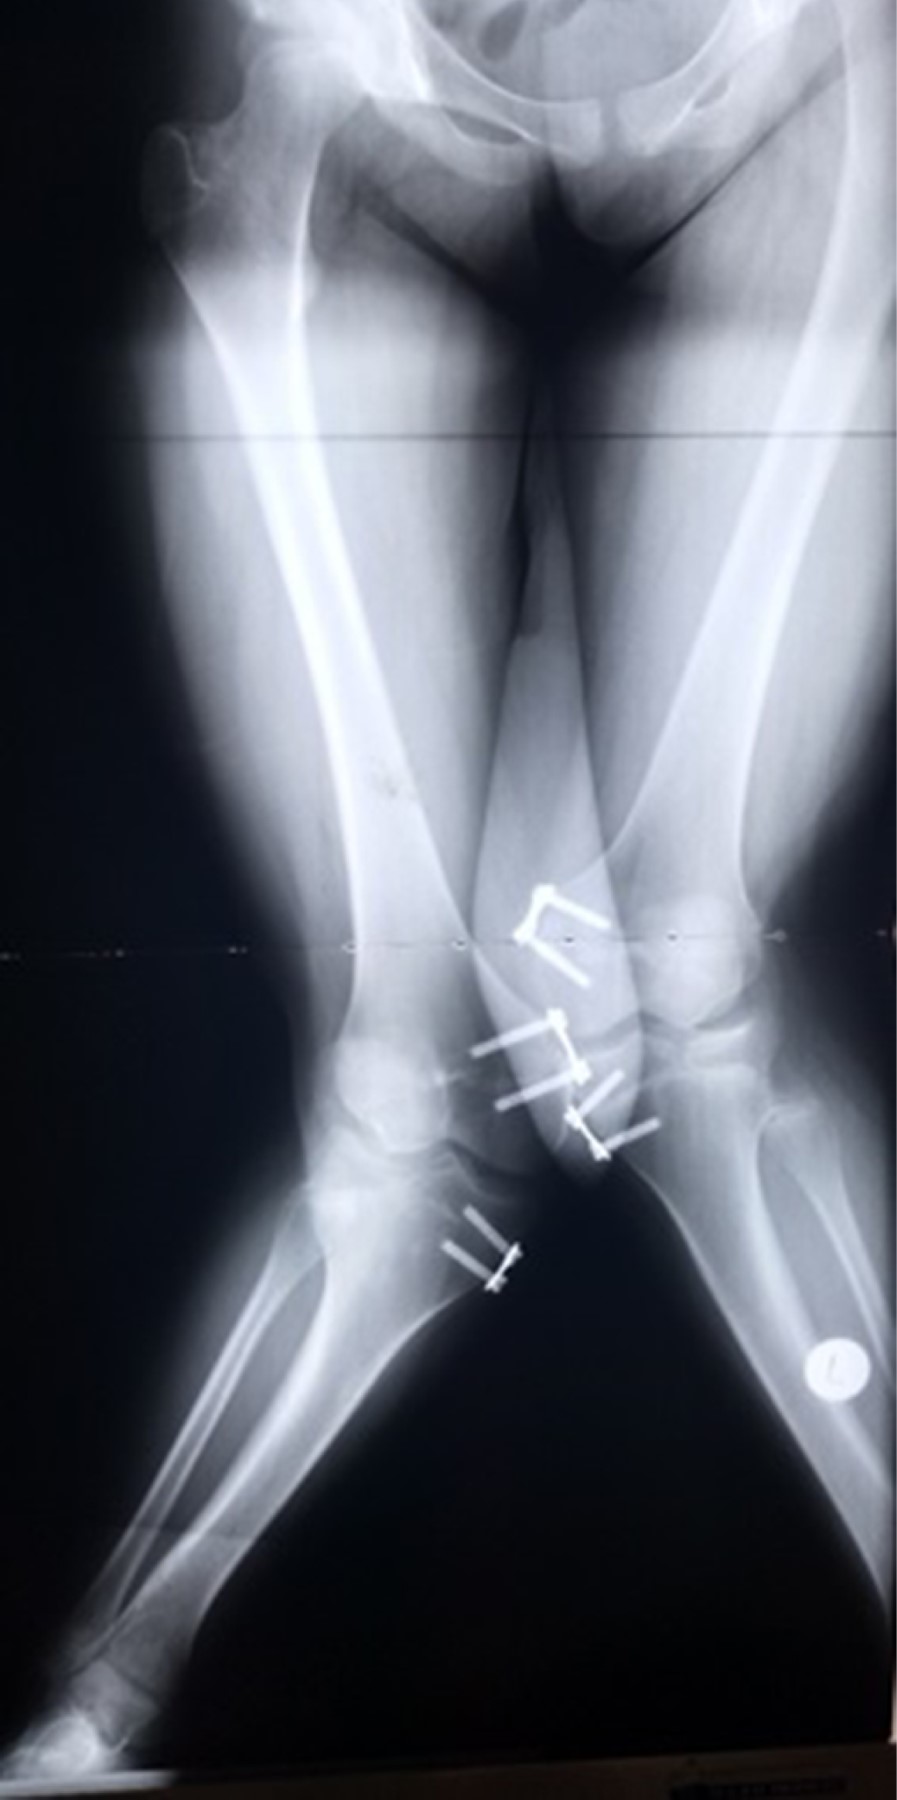

Se realizó la toma de radiografías panorámicas y segmentarias para una mejor planeación quirúrgica. Se encontró una depresión articular a nivel de plataforma tibial lateral bilateral, con valgo de rodillas de 44o derecha y 48o izquierda. Una MAD (desviación del eje mecánico) de 130 mm derecho y 122 mm izquierdo (Figura 1).

Para la planeación de la cirugía se tomó en cuenta que ambas extremidades contaban con una deformidad ósea compleja. Sin embargo, se observó mayor deformidad en miembro pélvico derecho, además de que el paciente contaba con mayor sintomatología en dicha extremidad. Se inició la primera intervención en tibia derecha a la edad de 15.4 años con una planeación preoperatoria, en la cual se realizó la medición del CORA (Center of Rotation of Angulation) con posterior osteotomía por debajo del mismo, considerando que éste se encontraba a nivel articular, se colocaron las bisagras en la cara convexa de la deformidad y con dos niveles proximales y dos distales para mantener la estabilidad del dispositivo. Se optó por una corrección progresiva con fijador circular Ilizarov para lograr una corrección gradual de la deformidad en valgo. Se realizó una cuña de apertura lateral que medializa y alinea el segmento distal, mejorando el trayecto del aparato extensor y la función de la articulación femoropatelar al lograr hacer paralelas las superficies articulares de la tibia (Figura 2).

Después de 10 meses se realizó la segunda intervención quirúrgica, realizándose una osteotomía de alineación con fijador externo articulado en fémur derecho. En este sentido el objetivo fue mejorar la alineación de la superficie articular distal del fémur; la bisagra lateral, a nivel diafisario, generó una traslación, pero mejoría del eje mecánico. Continuando a la edad de 16.9 años, es decir, seis meses de la cirugía en fémur derecho, se realizó una corrección progresiva con Ilizarov en tibia izquierda, bajo el mismo principio de colocación de bisagras que en la tibia derecha (Figura 3).

Figura 1

Figura 2

Figura 3